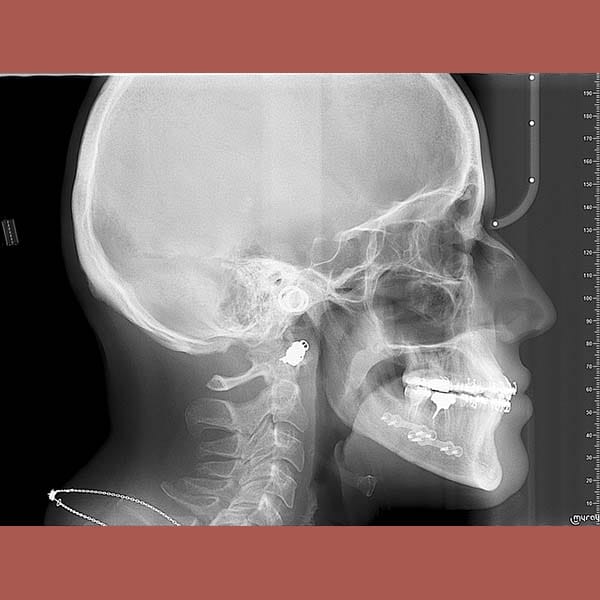

عندما يكون سبب المشكلة هيكلياً في عظم الفك، فإن تقويم الأسنان وحده قد لا يكفي. بصفتي خبير تقويم أسنان جراحي في الإمارات، أعمل بالتعاون مع جراحي الوجه والفكين. هذه الحالة توضح قوة الجراحة التقويمية للفك السفلي في علاج بروز الذقن والعضة المعكوسة بشكل جذري.

عانت هذه الشابة من بروز واضح في الذقن ناتج عن تقدم الفك السفلي، مما أثر على تناسق وجهها وسبب لها عضة معكوسة أمامية.

بعد شرح الخيارات، أوضح الدكتور خالد الكاتب أن تحسين العضة ممكن بالتقويم وحده، لكن تصحيح بروز الذقن يتطلب حلاً جذرياً. أصرت المريضة على الخيار الأفضل وهو الجراحة التقويمية. تمت الخطة على ثلاث مراحل: